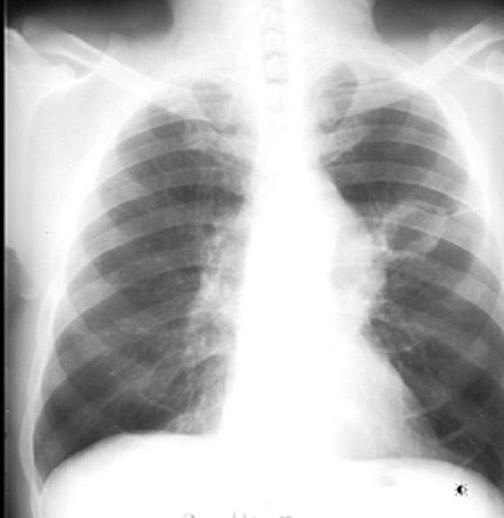

Case 2 Labeled Image What is the differential for multiple cavities?